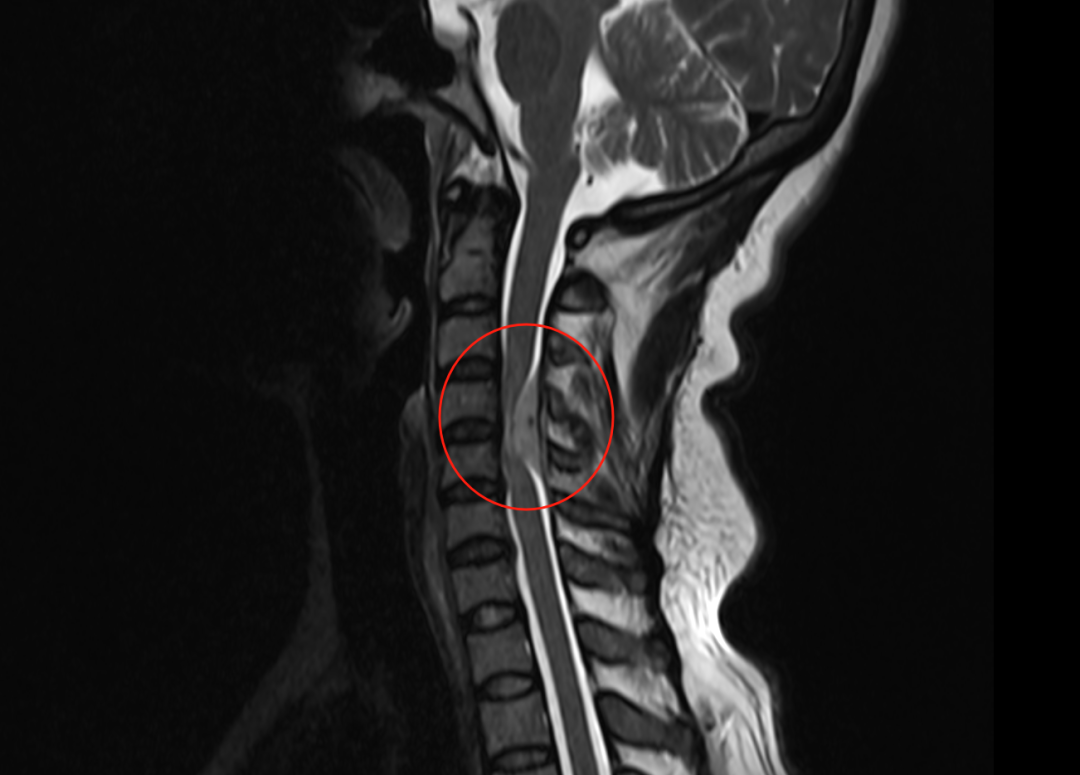

術(shù)前磁共振影像

接診她的神經(jīng)外科脊柱組胡永珍副主任醫(yī)師檢查后認(rèn)為,吳女士雖有腰椎間盤突出,但癥狀絕非腰椎間盤突出所致。醫(yī)生經(jīng)核磁共振檢查發(fā)現(xiàn),吳女士的第3-5頸椎水平節(jié)段髓內(nèi)占位,建議立即住院,完善檢查后行手術(shù)治療。